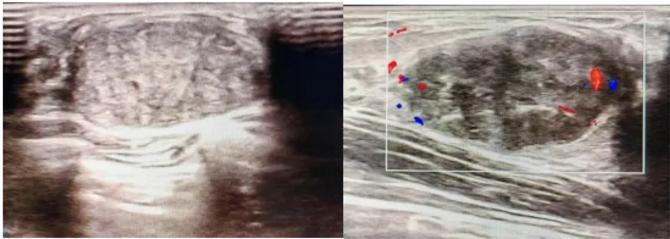

三、彩超檢查:無創(chuàng)檢查的“黃金眼”

高分辨率:可清晰顯示腫塊形態(tài)、血流信號,敏感度達80%-90%。

2.彩超報告關鍵指標

形態(tài):良性多呈橢圓形或分葉狀,邊界光滑。

縱橫比: 良性通常<1(橫徑>縱徑) 。

血流信號:纖維瘤血流較少,惡性常伴豐富雜亂血流。

鈣化:粗大鈣化多為良性,細小簇狀鈣化需警惕惡性。

BI-RADS分級:2-3類提示良性,4類以上需進一步檢查。

典型表現:

橢圓形低回聲團塊,包膜完整,內部回聲均勻,后方回聲增強,周邊無“蟹足樣”浸潤。